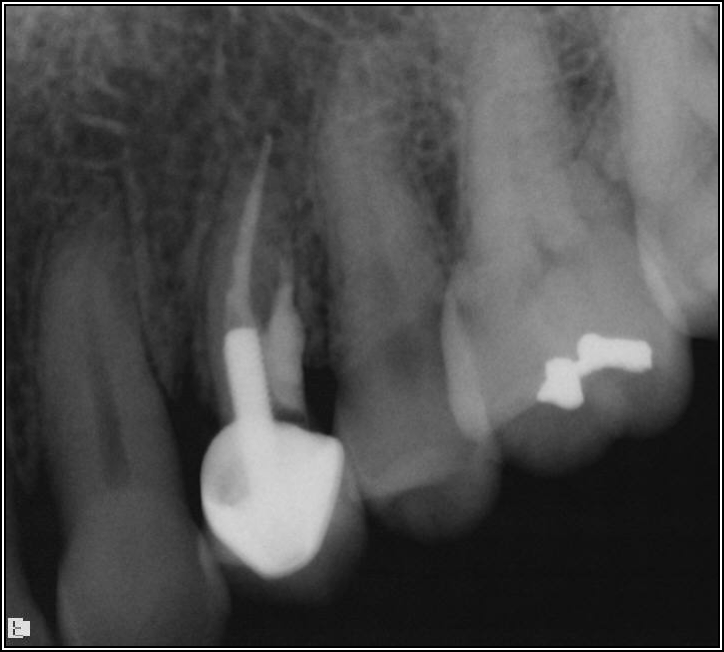

Fig 14. The post was shorter than ideal.

Figure 14

The rules for placement of a post depend on good retention: the greater the length, the greater the retention.3 Also, two-thirds of the length of the root is ideal, but 4 to 5 mm of apical gutta-percha is essential because anything less than that will disrupt the seal.8 Figure 14 shows a case where a patient had a post, core, and crown. The threaded post was shorter than ideal because the tooth was longer. Not visible was the mental foramen underneath. The patient did not have the financial resources to have the case redone. However, when the post would be removed, the clinician would need to trephine or use an ultrasonic around it, making the access bigger than an ideal conservative access. Potentially, the crown would come off. The patient did not have finances for re-treating the tooth and could not have an apicoectomy because the mental foramen was directly under the tooth.

The options, therefore, were to extract it and put a bridge or an implant in later when funds were acquired, or, as was done in this case, perform an intentional replant. The clinician extracted the tooth, cut it, placed MTA, and then put it back under occlusion using sutures—although the clinician would normally put composite in each corner to maintain it and would not etch. Usually after 2 weeks, there is stability. Figure 15 shows the postoperative radiograph, and Figure 16 shows a radiograph 4.5 years later. The patient's probing went from 3 to 4 mm, but overall it was a success because something is always lost coronally, whether the case is a replant or an implant.

Fig 15. Postoperative radiograph.

Figure 15

Fig 16. Radiograph after 4.5 years.

Figure 16